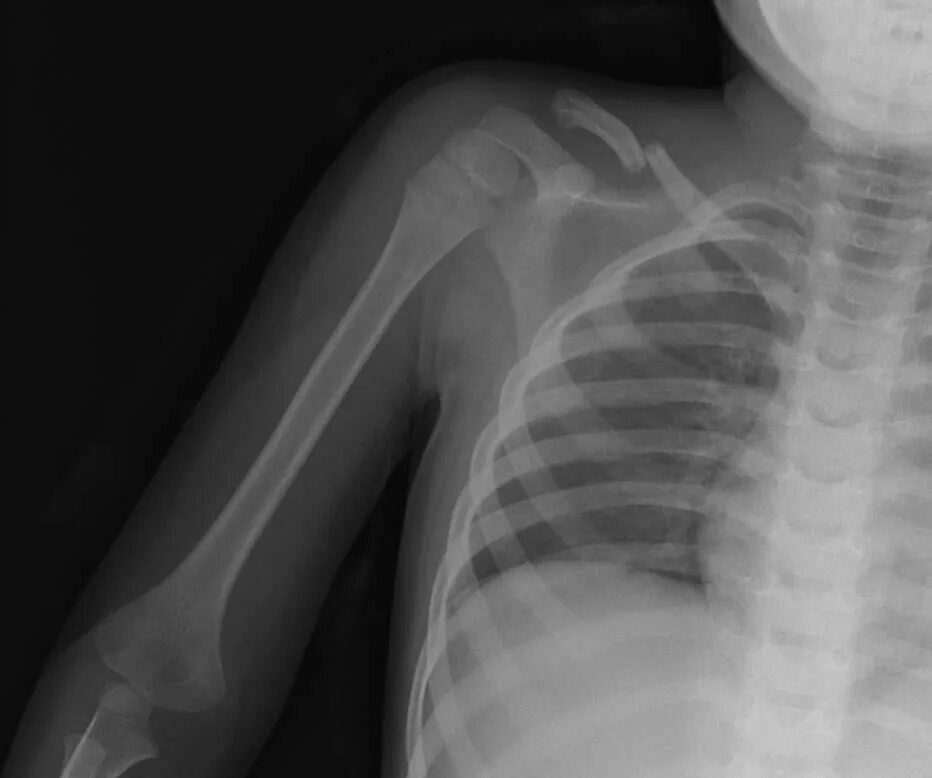

Множественные ребра